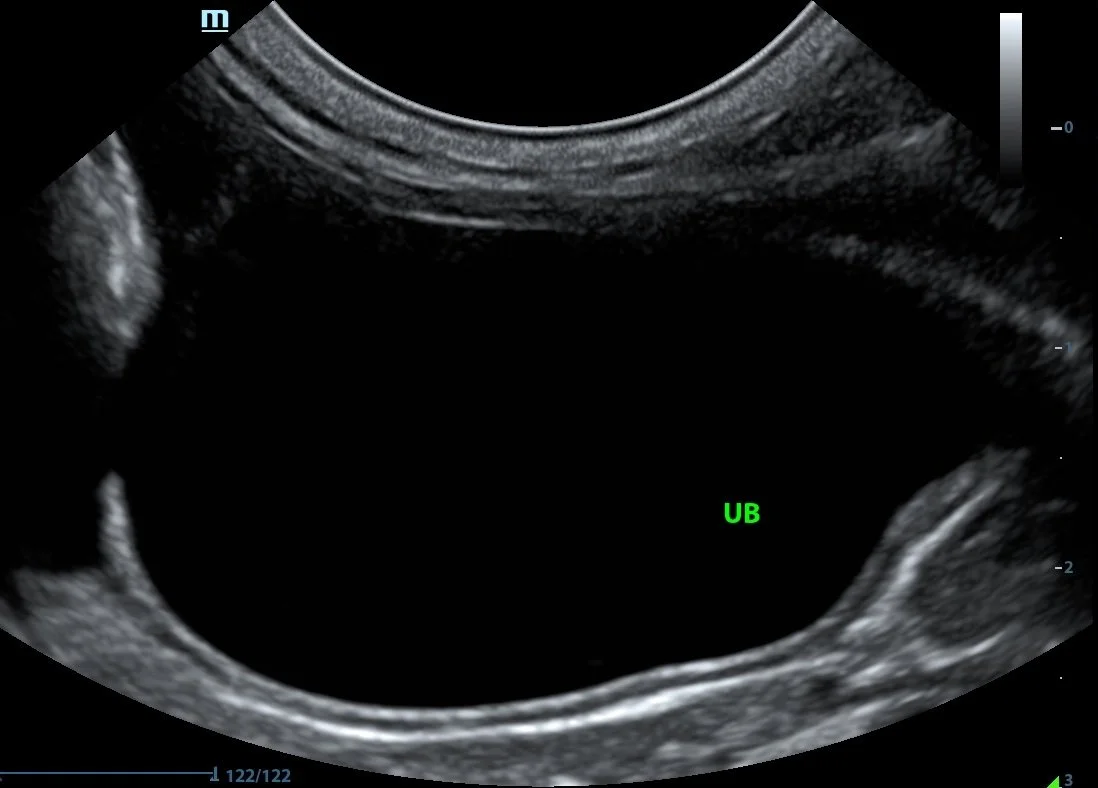

It is important to be aware of this artifact so that it is not mistaken for a real lesion. In the image of the urinary bladder below, edge artifact is creating the appearance of a defect in the wall.

Note the false defect in the apical wall of this urinary bladder caused by edge shadowing.